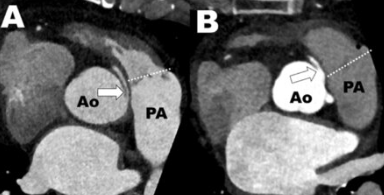

“Slit-lile” ostium

Anomalie avec naissance du sinus gauche, trajet interarteriel et “slit-like” ostium